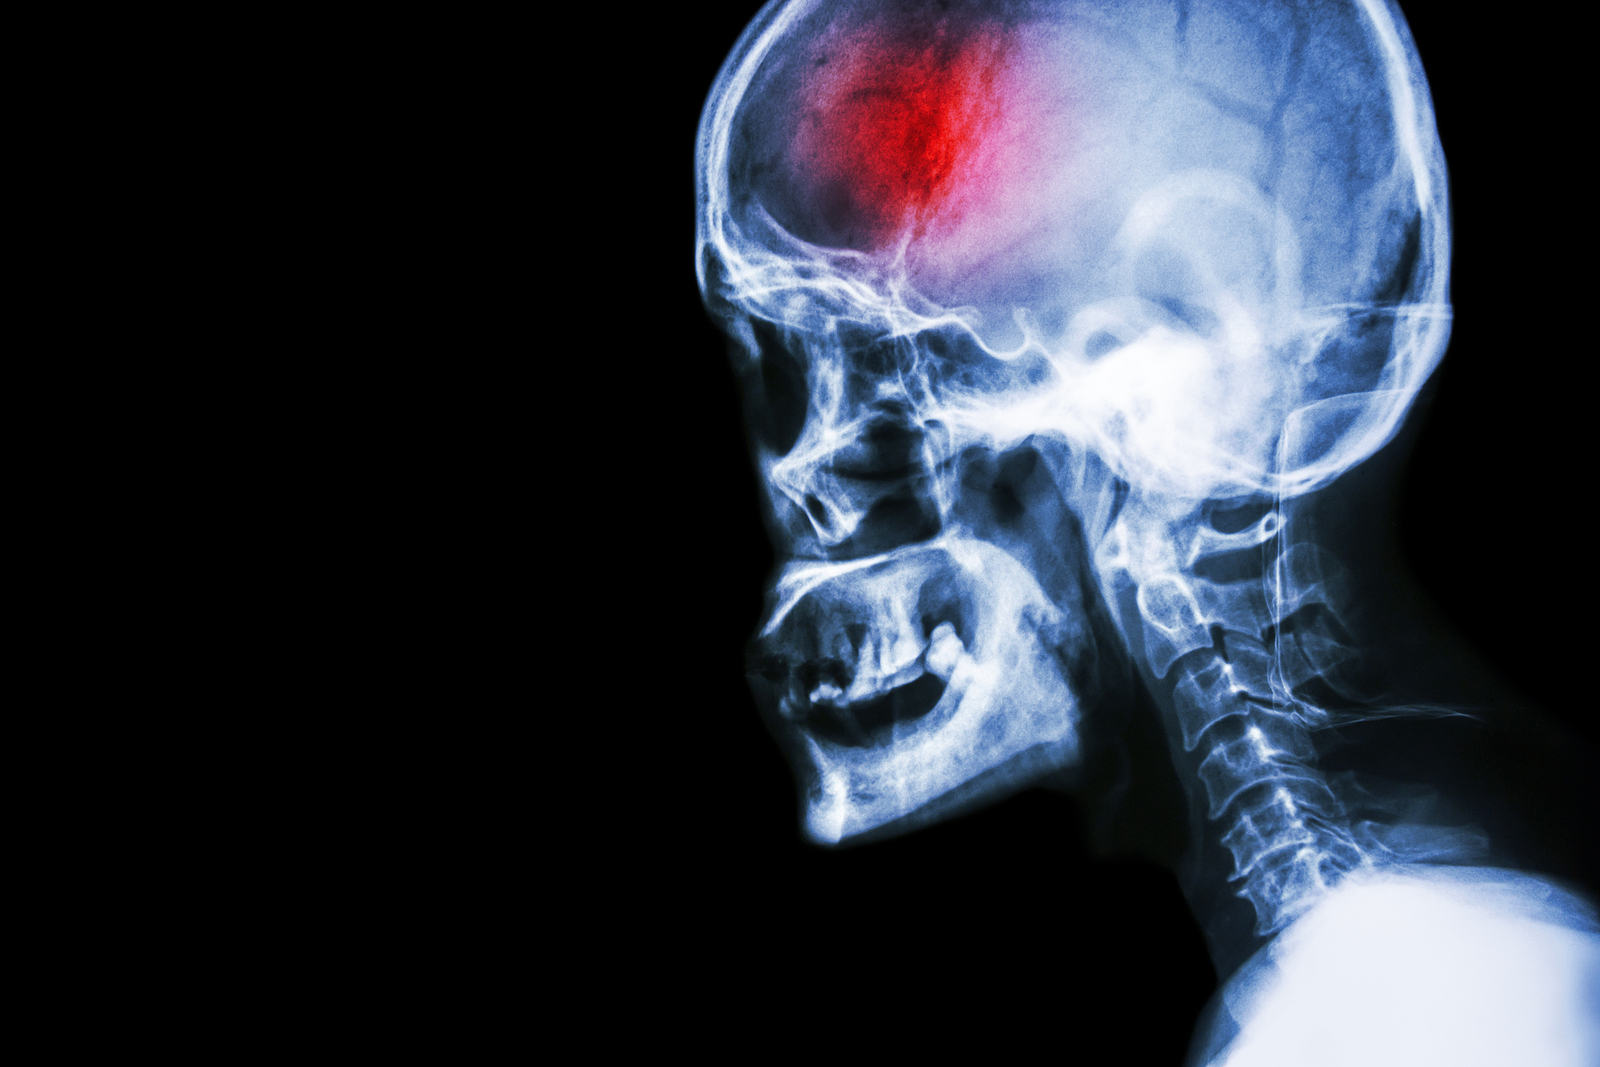

What is a stroke?

A stroke (previously known as a cerebrovascular accident) when there is a decreased flow of blood to the brain from either a blockage in the blood vessels that supply the brain (ischemic stroke), or a bleed from the blood vessels that supply the brain (hemorrhagic stroke). When the blood flow to the brain is blocked it prevents the brain from getting the needed oxygen and nutrients to function. Without oxygen the brain cells can be permanently damaged or die and the physical and mental functions related to that area of the brain will be affected. A stroke is a medical emergency and rapid treatment is crucial to decreasing the damage caused by a stroke.

Types of strokes

There are three types of strokes:

- Ischemic stroke: a stroke that is caused by a blockage (clot) that disturbs the blood flow to the brain.

- Hemorrhagic stroke: a stroke that is caused by a bleed that disturbs the blood flow to the brain and puts pressure on the surrounding tissue.

- Transient ischemic attack: often referred to as a “mini-stroke” or TIA, where the blood flow to the brain is temporarily disturbed and as a result causes temporary signs and symptoms of a stroke that resolve quickly .

Computed Tomography (CT) scan and/or Magnetic Resonance Imaging (MRI) scan: These tests are done on your brain and used to locate the exact location of the stroke and to determine if it has been caused by a blockage or a bleed. These tests can also help rule out other conditions that may be causing symptoms, such as an infection or a brain tumour